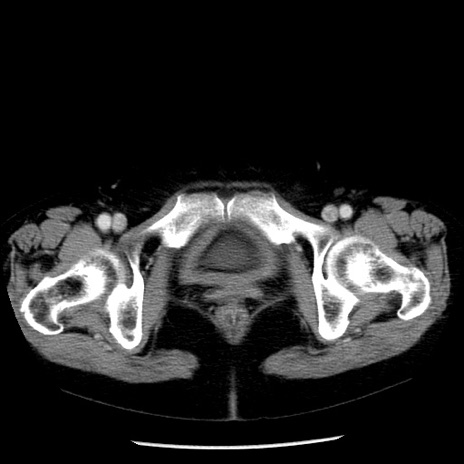

症例13(横断像)

【症例】70歳代女性

【主訴】腹痛、嘔吐

【現病歴】15時間程前(昨晩)より腹痛あり。今朝になっても症状の改善なく、嘔吐あり。腹痛も増悪あり、救急外来受診。

【既往歴】子宮癌全摘術後

【身体所見】意識清明、BP 121/72mmHg、P 74bpm、SpO2 100%(RA)、腹部:平坦・軟、腸雑音ほぼ聴取せず。下腹部・心窩部・臍左上に圧痛あり。反跳痛なし。

【データ】WBC 10600、CRP 0.15